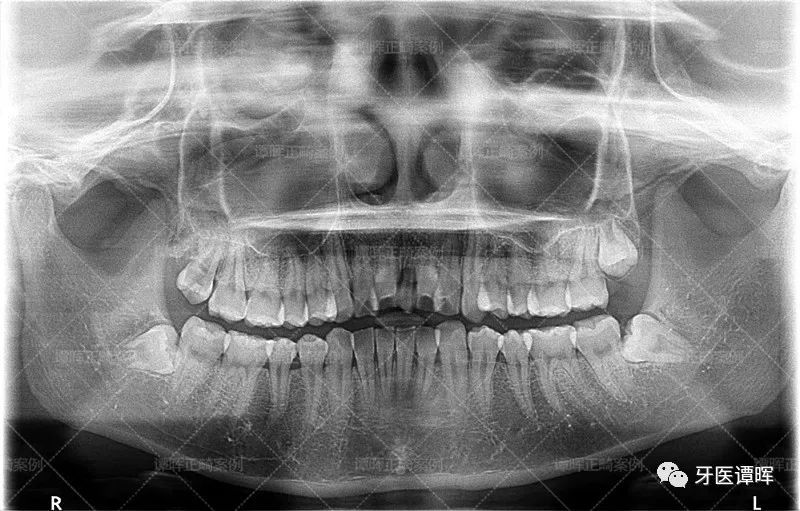

△X线分析:明显看出前牙往前突,上牙的侧切牙也是非常不齐。

俗话说:再漂亮的嘴唇遇到乱乱的一口牙也是一秒拉下神坛。因为前牙往外突,侧牙又往内收,中间门牙小,所以,前牙会显得有点大。如果开口说话,就会显得很不协调!